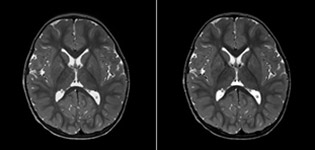

Philips mDIXON TSE is a two-point DIXON technique that separates water and fat signals, for time-efficient fat-free imaging, even in challenging neuro anatomy. “mDIXON TSE has been one of the most significant improvements in imaging sequences that we have utilized to date at PCH,” says Dr. Miller. “Its multi-parametric acquisition allows us to obtain fat suppressed images and equivalent non-fat suppressed T2 images all in the same sequence. In addition, prior methods of fat suppression could be artifactually corrupted by poor patient anatomy or poor operator application, but with mDIXON we now have a robust and reliable method of fat suppression.” Fat saturation is historically challenging at the ends of fields of view, especially in total spine imaging and in difficult patient anatomy such as the lower regions of the neck. “Due to the unique fat suppression capabilities of mDIXON, however, these challenges no long apply,” says Dr. Miller. “We routinely obtain homogeneous fat suppression under virtually all conditions. It has also led to some efficiencies by not having to repeat sequences because of that technical failure.”

“mDIXON TSE is most useful in patients with lesions or abnormalities in the soft tissues such as the face and neck, and for patients with contrast enhancing abnormalities that are mostly visible with fat suppression,” says Dr. Miller. “All our spine imaging now routinely contains mDIXON water-only T2 images, and this allows us to identify pathology that may be obscured by non-fat suppressed imaging such as injuries of the bone. And it’s not necessary to obtain additional standard TSE T2 images because the in-phase mDIXON images are equivalent to standard TSE T2 images.”